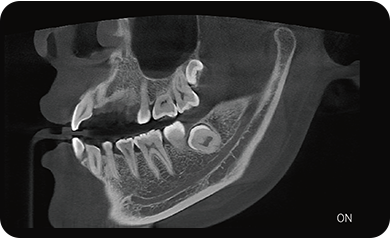

临床样片